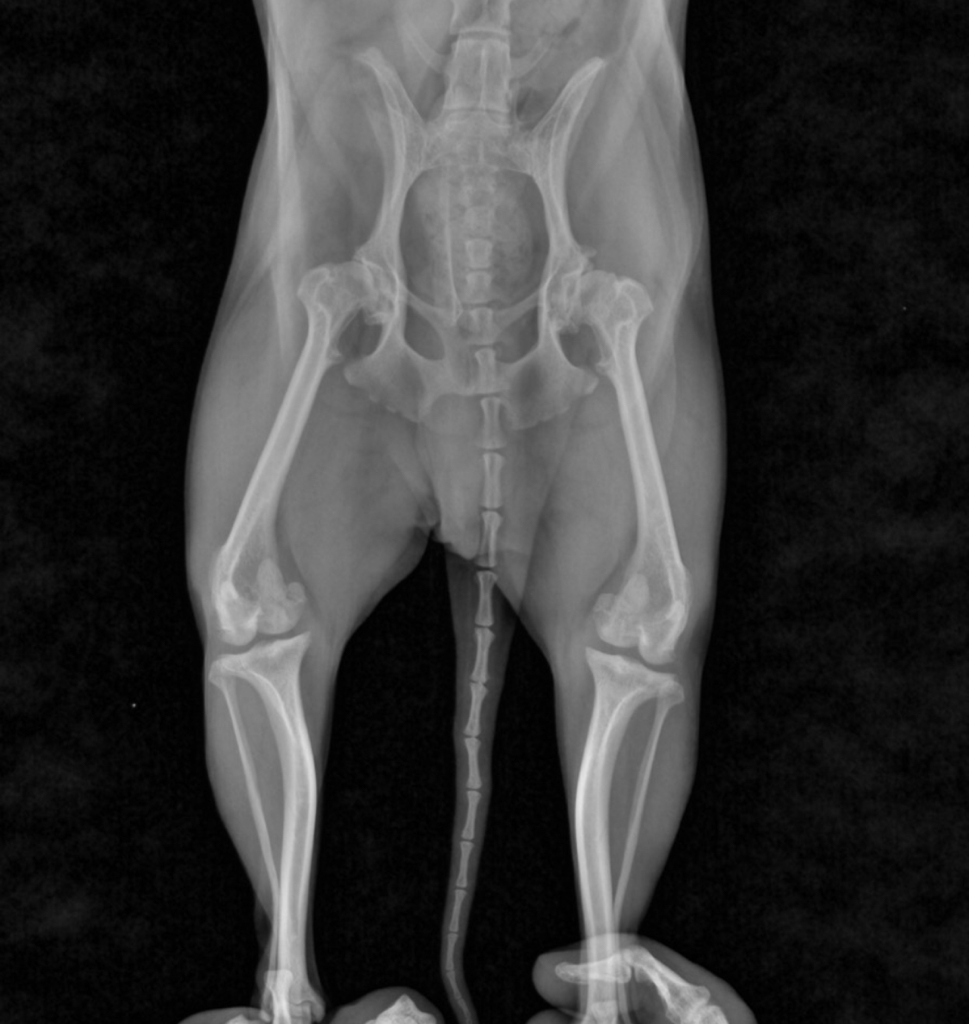

이번에 하부 엑스레이 찍은 사진인데 슬개골 보다 고관절이 조금 안좋다고 해요 지금 평소에 절거나 아파하진 않은데 사진상 보면 당장 수술해야 하는 정도인지 궁금해요.. 병원에서는 보호자 마음이라고 하시네요...

양쪽 고관절쪽에 이형성증이 있는듯하게 보이네요 사실 이런 진단학적인 요구는 아하에서 금지 입니다.

주치의 선생님께서는 이런 치료할 수 있는 방법들을 제시하고 선택과 결정은 보호자의 몫입니다.

고관절 수술의 경우 검사와 강아지의 증상의 여부에 따라 진행 하는 것이기 때문에 만약에 강아지가 증상이 너무 심해서 수술이 지시되어 다시 걸을 수 있을 확률이 예를 들어 80%이고 비용적인 부분과 입원기간 등을 수의사가 제시하는 것이기에 수술하고말고는 보호자의 몫입니다.